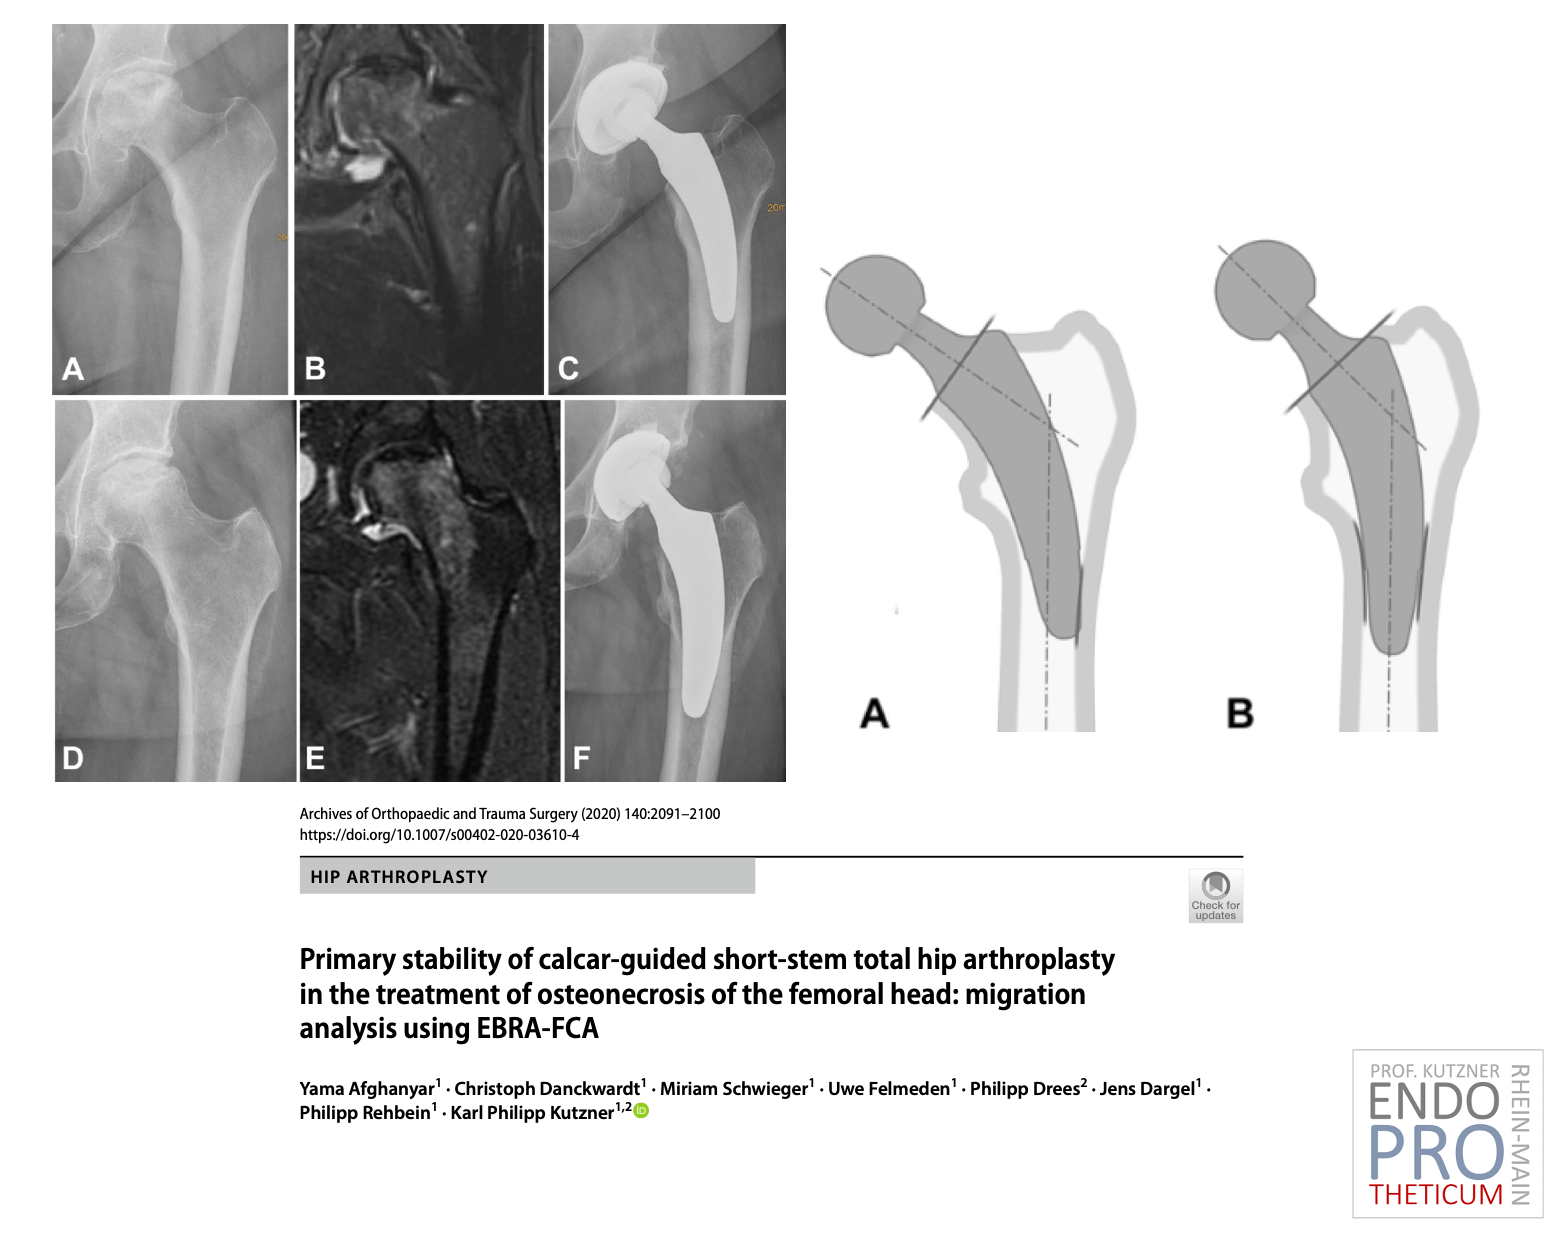

El concepto de vástagos cortos modernos guiados por calcar en la artroplastia de cadera tiene como objetivo la reconstrucción precisa de la geometría anatómica individual de la cadera. Se utiliza una técnica de implantación respetuosa con los huesos y los tejidos blandos junto con una carga fisiológica en la parte del fémur cercana a la articulación para preservar el hueso a largo plazo.